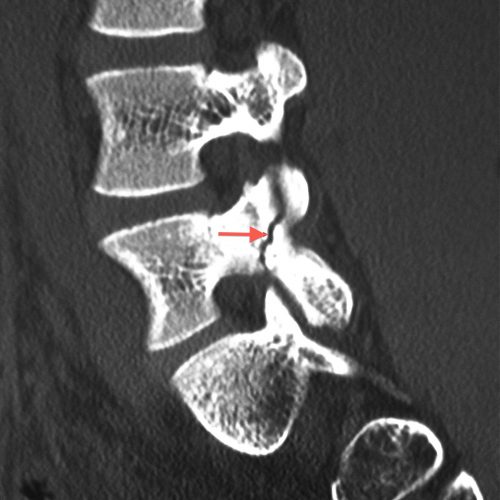

Espondilólise.